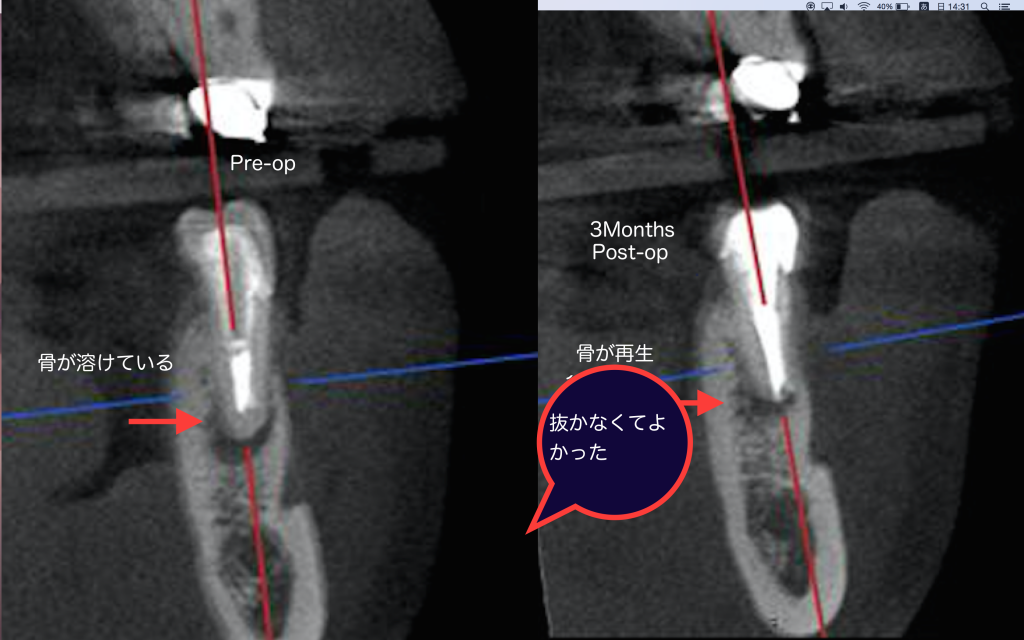

こちらの患者様は前医から歯が割れているかも知れないと抜歯を勧められましたが、根管治療により3ヶ月後治癒傾向を認めました。

正しく行われる根管治療の威力は素晴らしい。

しかしながらこのような結果になるのは、マイクロスコープ・CTなどの器械設備、術者の技量と長時間の治療時間が必要です。

今後は益々膿の部分が小さくなり、骨が再生すると思います。